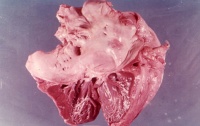

病理变化先瓣膜交界处和基底部炎症水肿赘生物形成,

二尖瓣狭窄

由于纤维化和(或)钙质沉着,瓣叶广泛增厚,粘连,腱索融合,缩短,瓣叶僵硬,导致瓣口变形和狭窄,狭窄显著时成为一个裂隙样的孔。按病变程度分为隔膜型和漏斗型。隔膜型主瓣体无病变或病变较轻,活动尚可;漏斗型瓣叶明显增厚和纤维化,腱索和乳头肌明显粘连和缩短,整个瓣膜变硬呈漏斗状,活动明显受限。常伴有不同程度的关闭不全。瓣叶钙化进一步加重狭窄,并可引起血栓形成和栓塞。先天性的二尖瓣狭窄,其瓣叶增厚、交界融合、腱索增厚或缩短、乳头肌肥厚或纤维化,瓣上可有狭窄环、瓣下可有纤维带。最具特征性是只有一个乳头肌的二尖瓣降落伞状畸形,两个瓣叶的腱索都连接在此乳头肌上,整个瓣膜开加降落伞。